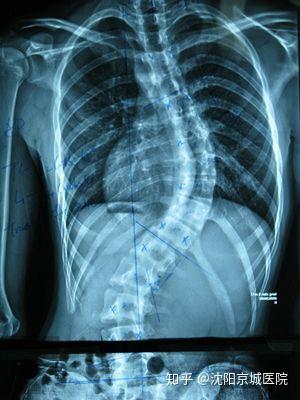

強(qiáng)直性脊柱炎的主要癥狀包括下腰部疼痛、僵硬和關(guān)節(jié)活動(dòng)受限,患者可能在早晨或長時(shí)間坐立后感到明顯的不適,隨著病情的進(jìn)展,癥狀可能逐漸加重,影響胸椎和頸椎,導(dǎo)致呼吸困難、駝背等,部分患者還可能出現(xiàn)疲勞、發(fā)熱、食欲不振等全身癥狀。

強(qiáng)直性脊柱炎的診斷主要基于患者的癥狀、體格檢查和影像學(xué)檢查,醫(yī)生可能會(huì)詢問患者的家族史和個(gè)人史,以了解可能的病因,血液檢查、X光、MRI等影像學(xué)檢查有助于確診強(qiáng)直性脊柱炎。